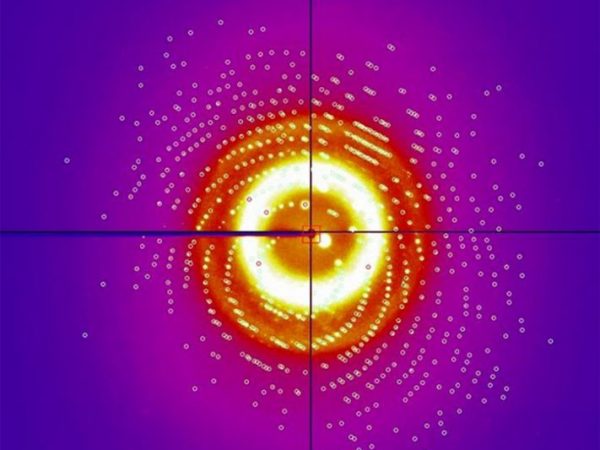

Crystals of a Breast Cancer Drug, David Ostrov, Arieann DeFazio, & Shun Lu

Interleukin 8 Flower, Arieann DeFazio

Interleukin 8 diffraction, Arieann DeFazio

Interleukin 8 abstract, Arieann DeFazio